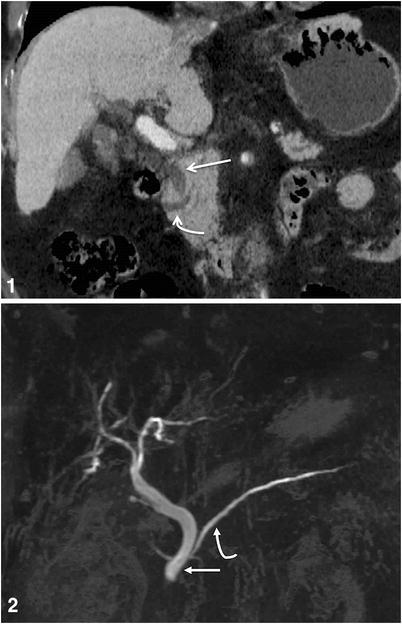

Crossing duct sign in Pancreas Divisum

failure of ventral and dorsal ducts to fuse

(duct of santorini is superior and drains to small (minor) papilla) while CBD always drains to major papilla

–> in divisum, main pancreatic duct drains into santorini and minor papilla, while wirsung only drains a small amount of pancreas and drains w CBD into major papilla